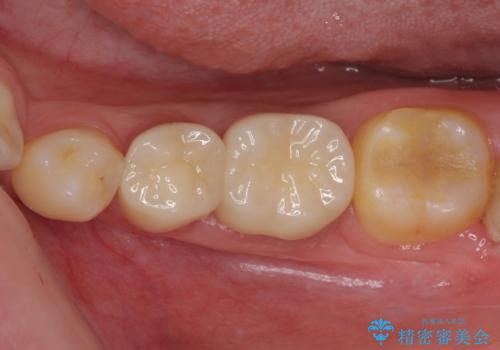

前歯のクロスバイトは、改善の途中で歯髄壊死を起こすリスクが高くなるため、マウスピース矯正よりもワイヤー矯正をお勧めしております。

この患者様もクロスバイトはあっという間に改善され、1年強で速やかに治療を終えることができました。